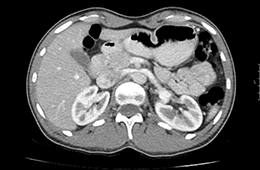

Die CT wird bei diversen Erkrankungen zur Klärung von Organveränderungen, Blutungen und Flüssigkeitsansammlungen sowie auch bei Tumorverdacht durchgeführt. Auch Verengungen und Verkalkungen in den hirnversorgenden Gefässen, der Körperschlagader, den Herzkranzgefäßen oder Tumoren im Darm können heute mittels CT nachgewiesen werden. Hinsichtlich bestimmter Erkrankungen der Lunge und des Bauchraumes und hinsichtlich der Untersuchung von schwerkranken oder beatmeten Patienten gibt es derzeit häufig keine strahlungsfreien Alternativen. Die CT ist daher in vielen Fällen eine unverzichtbare radiologische Methode zur Erfassung krankhafter Veränderungen im menschlichen Körper, deren Nutzen das Strahlenrisiko bei weitem übertrifft.

Bei Untersuchungen des Bauchraumes wird häufig verdünntes Kontrastmittel oral verabreicht, das in zwei Bechern über etwa 45-60 Minuten getrunken wird.